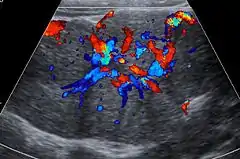

Unenhanced CT or MRI usually does not show the difference in intensity between the FNH and surrounding liver except when there is marked liver steatosis that reduces the attenuation of the liver, causing FNH to be hyperattenuating when compared with the surrounding liver. In the arterial phase CT or MRI, there is a strong enhancement not followed by washout. The lesion presents a slight hyperintensity or isodensity on portal venous phase or delayed phase images. There is also a presence of a central scar and absence of a capsule for the FNH.[5]